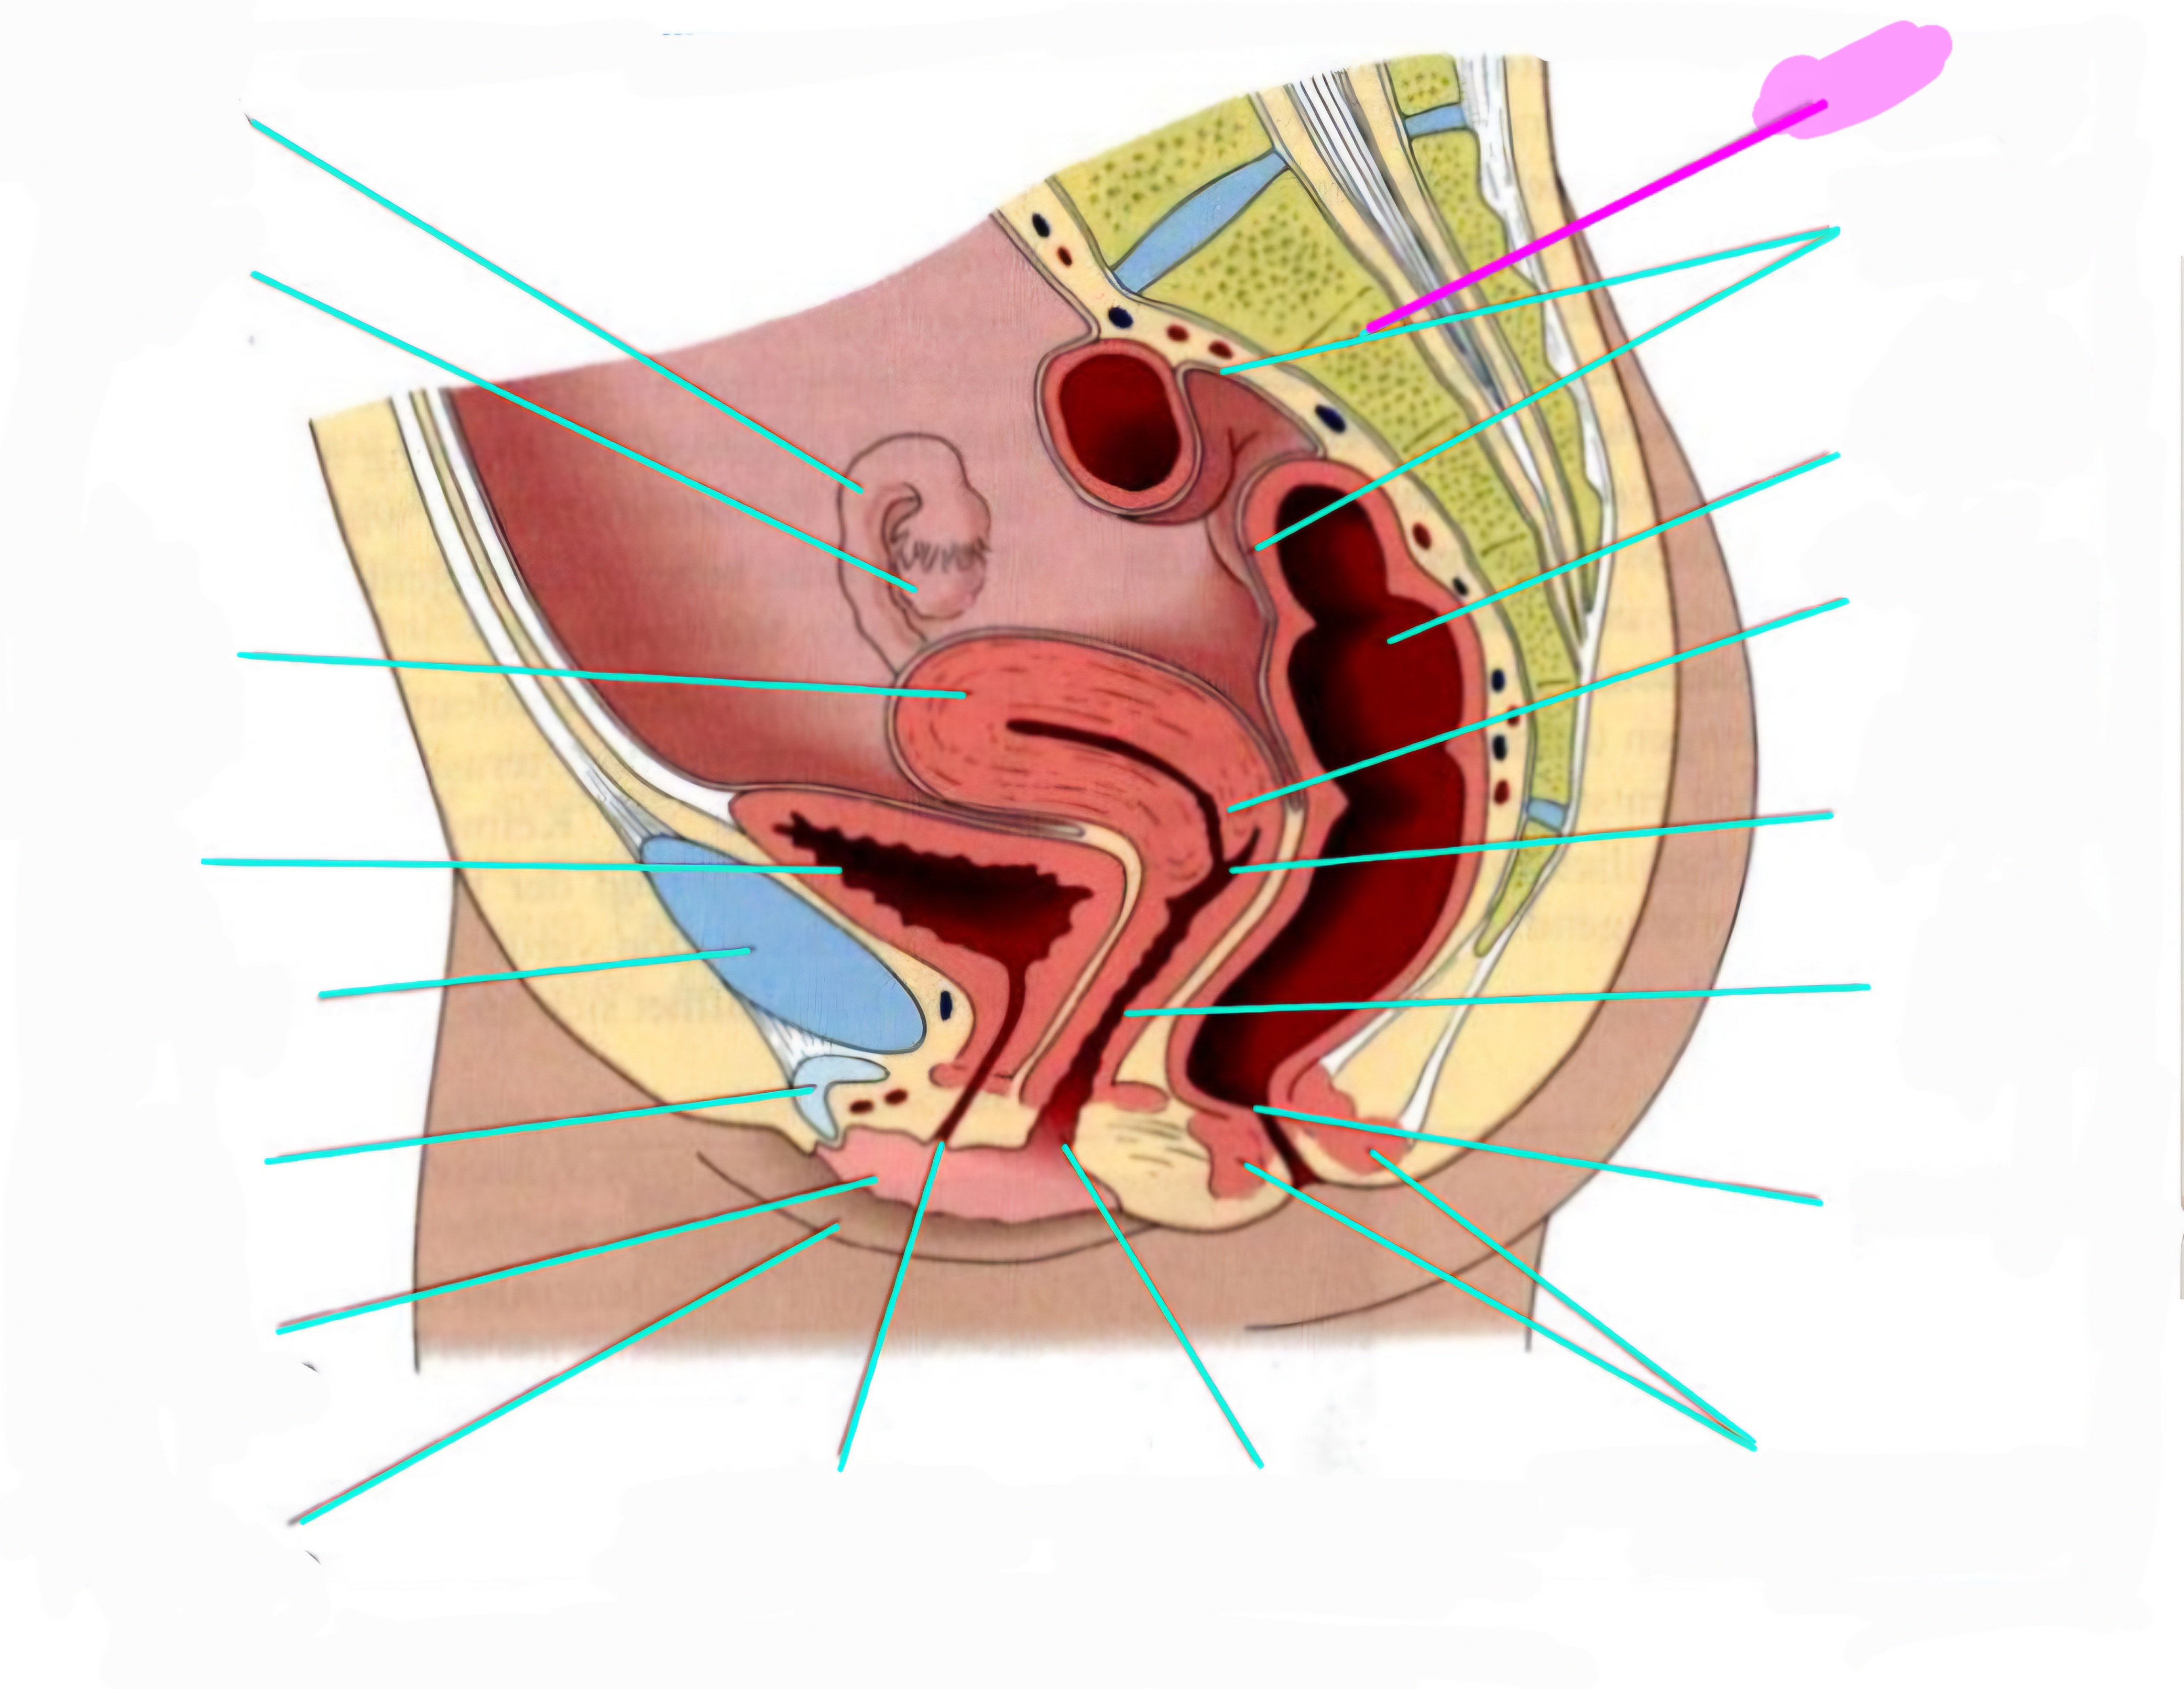

wbl. genital Anatomie

19 Terms

Tubea uterina (Eileiter)

Ovar (Eierstock)

Uterus (Gebärmutter)

Vesica Urinaria (Harnblase)

Symphyse

Klitoris

Labia minor pudendi (kleine schamlippen)

Labia Majoran pudendi (große Schamlippe)

Urethra (Harnröhre)

Introitus vaginae (Scheideneingang)

Sphincter ani externes (äußere Afterschließmuskel)

Anus (After)

Vagina (Scheide)

Portio (äußerer Muttermund)

Rektum (Mastdarm)

Zervix (Gebärmutterhals)

Peritoneum (Bauchfell)

Os sacrum (Kreuzbein)